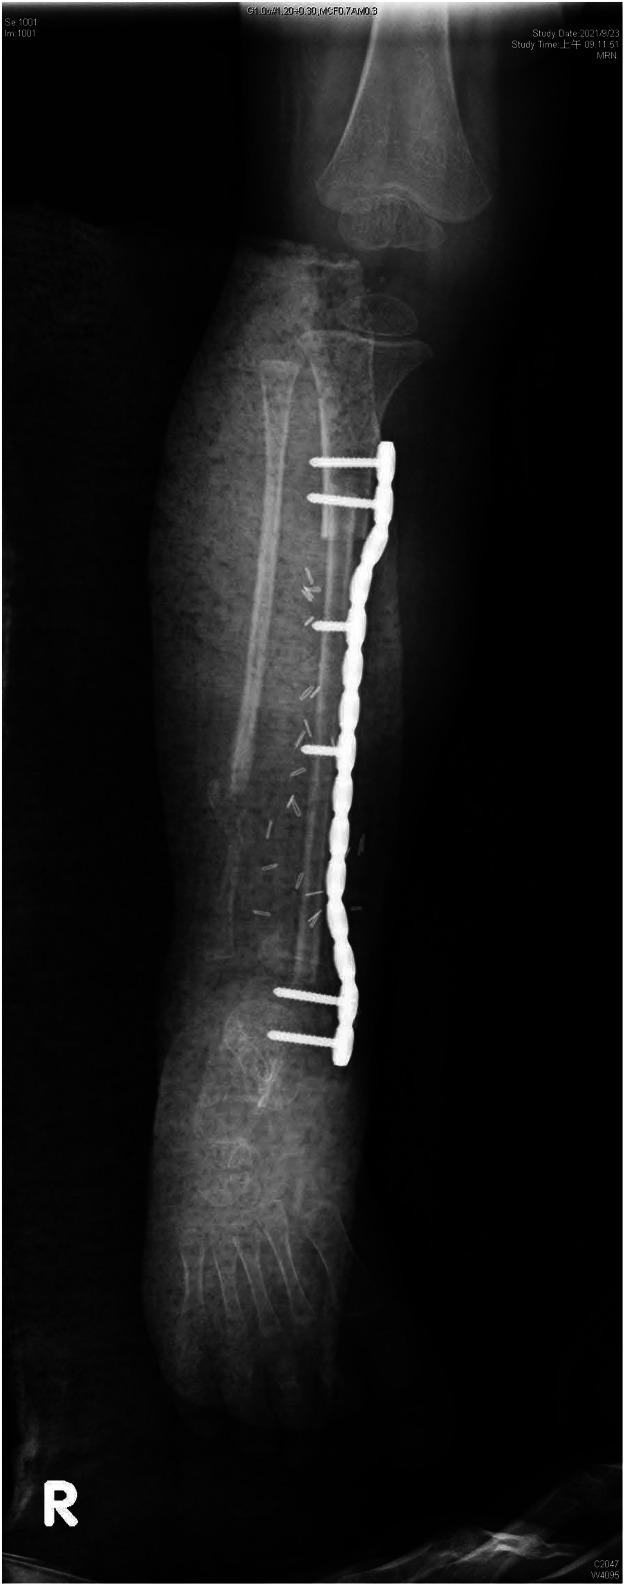

Congenital pseudoarthrosis of the tibia (CPT) is a rare pathological disease associated with neurofibromatosis type 1 (NF1). It presents with tibial bowing and can progress into a nonhealing fracture. Treatment options include conservative approaches such as serial bracing or various surgical options.Surgically, the aims are to achieve long-term bone union, prevent limb length discrepancies (LLDs), and avoid mechanical axis deviation, soft tissue lesions, nearby joint stiffness, and pathological fracture.The purpose of our study is to highlight our experience with both the conservative approach and the use of vascularized free fibula reconstruction of these deformities, including the challenges encountered with a long-term follow-up until skeletal maturity.

We present a retrospective analysis of a total of nine (9) patients consisting of three (3) girls and six (6) boys. Six (6) children were treated with a vascularized fibula flap, and the other three (3) were treated conservatively. Outcomes measured included fractures, LLD, ankle valgus deformity, donor site morbidity, and number of surgical corrections.

All patients had flap survival. Three (3) of six children had a previous failed surgery with intramedullary nail and bone graft prior to performing a vascularized free fibula reconstruction. The follow-up period ranged from 8 months to 200 months. The complications included stress fractures (50%), LLD (66.6%), and ankle valgus (33.3%). During growth phases, these children required multiple corrective surgeries.

Fibula free flap is a good treatment option for CPT even in patients with prior surgical failures with variable results. - Level 4 - Case series Therapeutic Studies-Investigating the Results of Treatment.